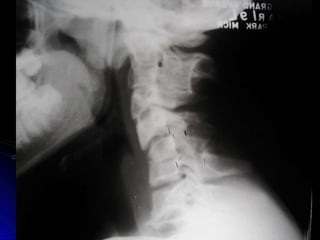

Cervical Lateral

Estructuras Visualizadas

•Cuerpos Vertebrales C2-T1

•Espacios Discales

•IAO (ADI)

•PE’s, Lámina, Pedículos,

•Pilares Articulares y Facetas

•Sombra Aire Traqueal

•Línea de George & línea Espino-laminar

•Silla Turca

•Arcos C1

Partes Blandas Prevertebrales

● Espacio medido entre los cuerpos

vertebrales y la sombra de aire de la faringe,

laringe y tráquea.

● Normalmente 10 mm en C1

● 4-7 mm en C4 (retrofaringeal)

● 20-22 mm en C6 (retrotraqueal)

Regla de 2’s y 5’s:

No más de 5 mm

en C2, o 22 mm en

C5